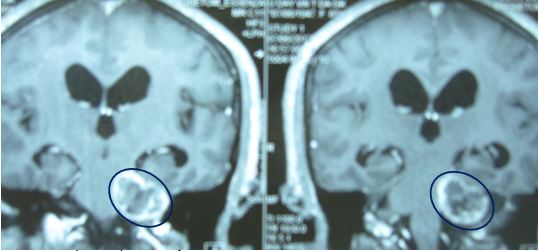

Trường hợp 4: Bệnh nhân nam, 65 tuổi vào viện vì đau đầu, ù tai trái, mất thính lực, có bệnh kèm theo là đái tháo đường,tăng huyết áp. Chụp MRI chẩn đoán: U dây thần kinh số VIII bên trái, kích thước 3,5cm. Bệnh nhân không có chỉ định phẫu thuật mổ mở. Xạ phẫu bằng dao gamma quay với liều 14 Gy.

Trước điều trị: U dây VIII trái 3,5 cm, u ngấm thuốc mạnh.

Sau điều trị 6 tháng: u hoại tử.

Hình 5: Hình ảnh MRI u dây thần kinh số VIII trước và sau xạ phẫu gamma quay